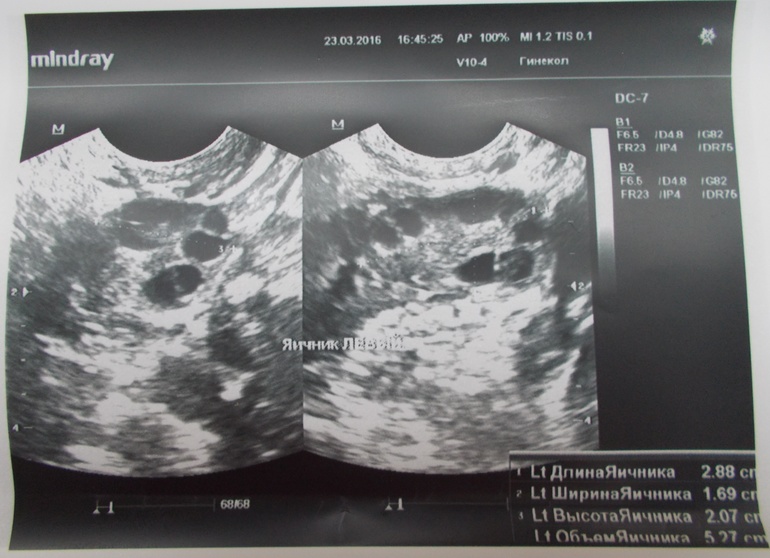

Доминантных фолликулов НЕТ(((( цикл снова пролётный(((овуляции не было и не будет((но что тогда со мной происходит?третий день какие-то боли внизу живота (как схватками), чувствую левый яичник, а сегодня утром и правый проснулся(думала, что это к приближающейся О, а вот и нет(

ЗАКЛЮЧЕНИЕ Ставят мультифолликулярные яичники!!!узистка долго сомневалась писать такое заключение или нет, но всё-таки написала....((( ещё сказала, что в шейке матки есть малюсенькие кисты!других паталогий не выявлено!

Снимки прилагаю.

Если есть комментарии по поводу снимков, пишите, потому что я в них вообще ничего не понимаю!